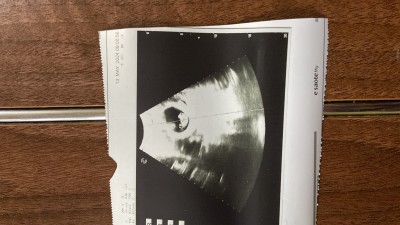

Gebelik haftası 9+5

Dr soylemedi mi anlamadim 2 kese gozukuyor

Ama o gözüken ikinci şey ne gaz diyen oldu da gaza da benzemiyor bence sizce

Canım ben ikiz  doğum yaptım 19 gün önce evet ben dedim gaz diye çünkü haftalık usg'ye girdim bebeğin yanındaki plasenta oluşuyor o yandaki ise hava boşluğu yani gaz evet zaten ikiz en geç 7. Haftada belli oluyor 9da ise 2.inci bebek kalp atışı ve ölçümü alınıyor şayet ikiz olsaydı seni riskli gruba yeşil alan açıp  kontrol isterdi çünkü ikiz takip tek gebelik gibi ilerlemiyor ... Yinede ben emin olmak istiyorum dersen bir daha git doktora ben ikiz görüyorum de o zaten detaylı açıklama yapacaktır....

İkincisi yolk kesesi olabilir diğer adıyla beslenme kesesi ikiz olsa doktorunuz söylerdi

Evet iki kese ve iki bebek görünüyor yani öyle gördüm ben